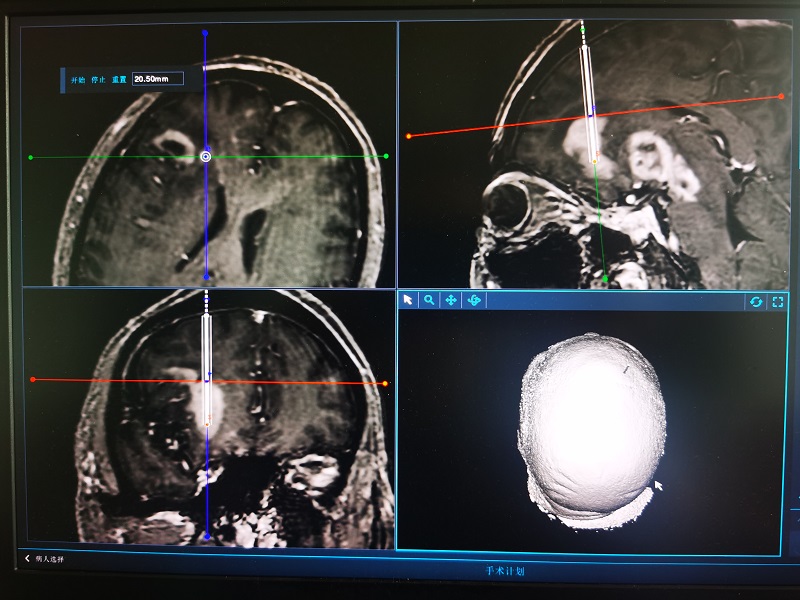

8月3日,中南大学湘雅三医院神经外科功能团队运用3D结构光机器人辅助新技术成功为一位脑深部病变患者施行活检手术。

患者李先生,64岁,是一位颅内多发病变患者。由于患者术前患者状况不佳,无法耐受长时间佩戴框架或其他耗时较长的立体定向手段,但病情又急需明确诊断指导下一步治疗,遂在医院神经外科的医生建议下决定采用3D结构光机器人辅助新技术进行活检手术。该手术方式大大节省了术前准备的时间,能最大限度的减轻病人的痛苦。8月3日,患者顺利完成手术,并在术后第3天得到病检结果,明确了下一步的治疗方案。目前,患者已暂时出院,等待下一步治疗。

目前,我国自主研发的3D结构光注册技术上处于国际领先水平且具有显著的临床应用价值。3D结构光注册技术类似手机面部解锁技术。配备3D结构光技术的神经外科手术机器人,在手术开始前随机扫描面部3-5次即可,手术准备时间由原先的近2个小时缩短至2分钟以内,为神经外科医生带来了极致精准、方便快捷的手术辅助体验,让临床术式不断的超越和突破成为现实。

该手术还有以下几大优势:一、免标志物注册,分秒必争。该手术无需术前安装头架、安放标志物(Marker),无需加扫当日术前定位CT,无需医生手动拾取标志物,3D结构光定位仪全自动进行无接触的、快速的扫描注册及精度验证,注册过程整体耗时<2分钟,大大节省了术前准备时间,急重症术式也能轻松应对。二、整头范围扫描,无限体位。3D结构光定位仪可对患者头部进行大范围、多角度、多姿态的点云扫描,并获得完整的三维头面部点云,从而让方便快捷的无标记点注册技术不再受患者体位限制。三、定位精度0.5mm,极致精准。3D结构光定位仪可瞬间获取患者头部百万量级的高密度点云,实现小于0.5mm的注册定位精度,完美的满足了医生对于注册便利度、速度和精度的所有要求。